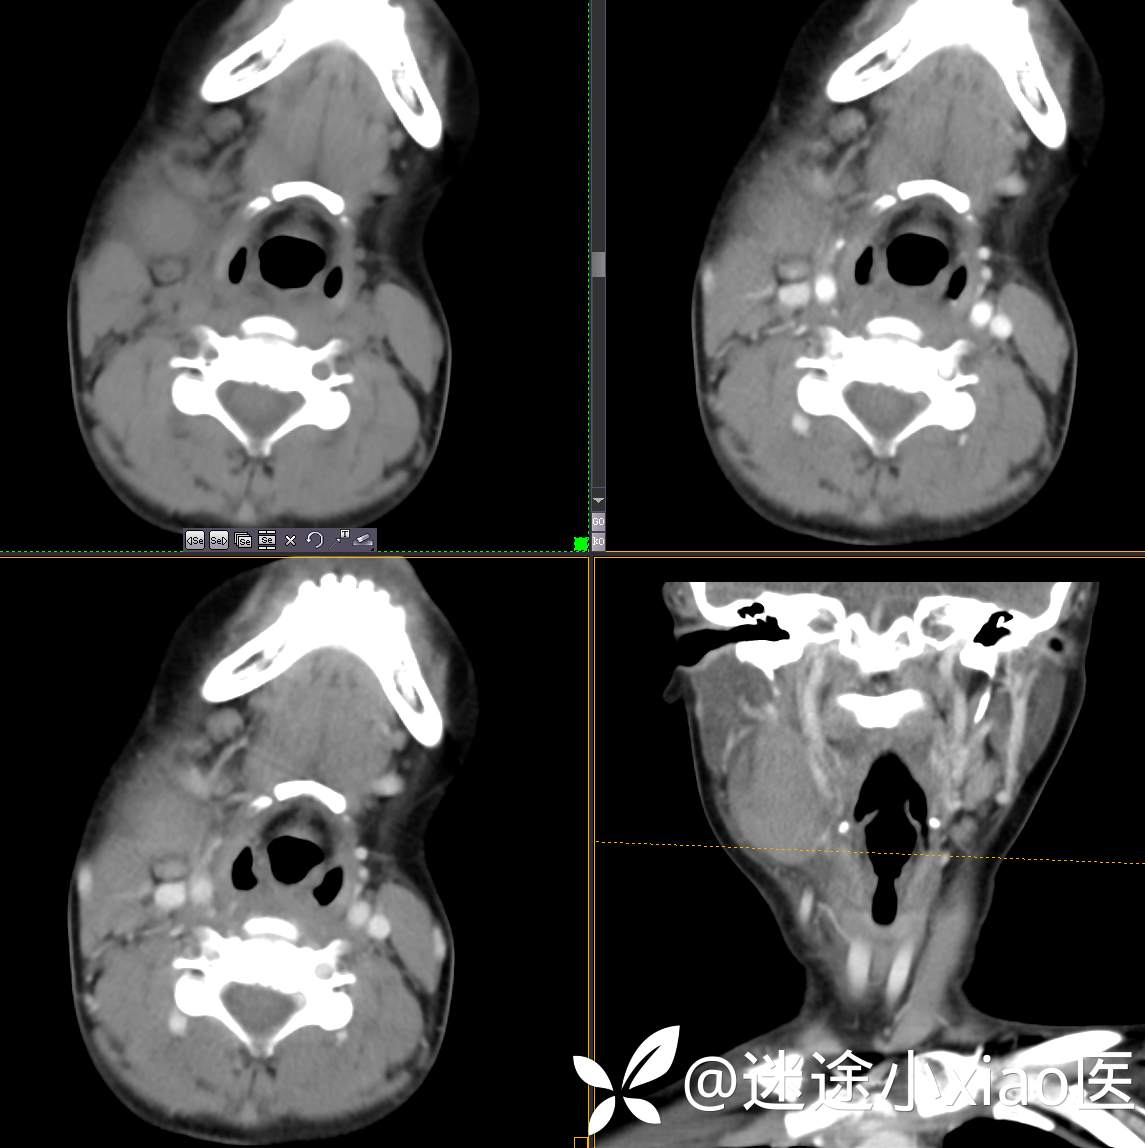

头颈组16:青少年女性,发现右颈部肿物半月余,感染?肿瘤?

现病史:患者半月余前无明显诱因下发现右颈部肿物,大小4.2*2.1cm,局部无红肿,皮温正常,有压痛,感头晕头痛,无其他不适。查甲状腺及颈部淋巴结B超提示:双侧甲状腺多发结节;右侧多发肿大淋巴结。初步诊断为“淋巴炎”,予“头孢类”抗生素抗感染治疗12天(具体药物不详),自觉肿块胀痛缓解,头晕头痛症状仍存。